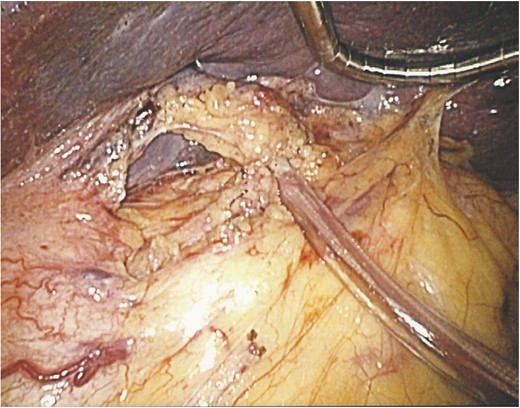

Under general anaesthesia, the patient was placed in the right lateral position. Laparoscopic surgery proceeded with four ports in the left upper abdomen (Fig. 3). Then under 15 mmHg capnoperitoneum, the spleen was retracted using a 5-mm diamondflex retractor (Lina Medical, Devon, UK). A large simple–appearing splenic cyst was demonstrated, arising from upper pole of the spleen, with some inflammatory adhesions to the under surface of the left lobe of liver and diaphragm. The splenic hilum was exposed after dividing the gastrospelnic ligament and the hilar vessels were slung in a Nylon tape. The adhesions were divided using the Thunderbeat coagulation device (Ethicon, Livingston, UK). The slung splenic hilum was clamped by advancing a plastic tube (a mid-section of a nasogastric tube) over the Nylon sling and fixing it in position with a haemostat applied outside the abdomen (Fig. 4). The cyst was then decompressed by aspirating its clear straw-coloured fluid content which enhanced exposure and access. De-capsulation of the cyst was performed using the Thunderbeat coagulation device to include the thinned part of the spleen over the cyst, with removal of ~90% of the cyst wall. The remainder of the intra-splenic portion of the cyst wall was sprayed with diathermy to destroy its lining epithelium. The splenic edge was treated with Floseal Haemostatic Matrix (Baxter Helathcare S.A, Zurich, Switzerland) and a sheet of Surgicel (Gelita Medical, Eberbach, Germany) was applied to an oozy part and was oversewn over the spleen edge with Vicryl 4/0 in a continuous manner. The hilum was unclamped after a total ischaemia time of 30 min and no bleeding was encountered despite reducing the intraperitoneal pressure to 7 mmHg for 3 min. The spleen appeared well perfused (Fig. 5).

An operative image showing the splenic hilum slung with the vascular tape and clamped with a segment of a nasogastric tube.

In this report, we describe for the first time a new approach that involved slinging and clamping the splenic hilum on a vascular tape, which enabled a bloodless approach to a radical de-capsulation without the need to tackle smaller arterial branches, avoided tedious bleeding that could have obscured the surgical field, and avoided taking down small arterial branches with the potential of segmental infarction of the spleen. This manoeuvre resembles in principle the Pringle manoeuvre [9] commonly used in liver resection. This approach can be added to the armamentarium of the laparoscopic surgeon to simplify a more radical resection of simple splenic cysts.